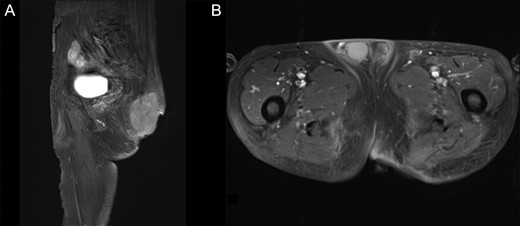

Two months after initial examination, the patient was hospitalized at our department. To prevent a secondary infection from defecation, we first performed an artificial anastomosis. Mohs’ paste was subsequently applied a total of 16 times over 3 months. The wound infection improved 2 weeks after administering Mohs’ paste and antibiotics (ampicillin/sulbactam). After the infection subsided, three courses of neoadjuvant chemotherapy (Doxorubicin) were performed. The disintegrated portion of the tumor recessed by using Mohs’ paste, and the bleeding, exudation and odor subsided. Moreover, the patient was able to tolerate both sitting and supine positions (Fig. 1B). The contrast-enhanced MRI revealed that the protruding area of the tumor was resected with no increase in the internal tumor size (Fig. 3A and B). One day prior to curative surgery, embolization of the left inferior gluteal artery.

Pre-operative T1WI contrast-enhanced MRI with fat suppression. (A) Sagittal image. (B) Axial image. The protruding tumor was resected, and the internal tumors showed no considerable changes in size.